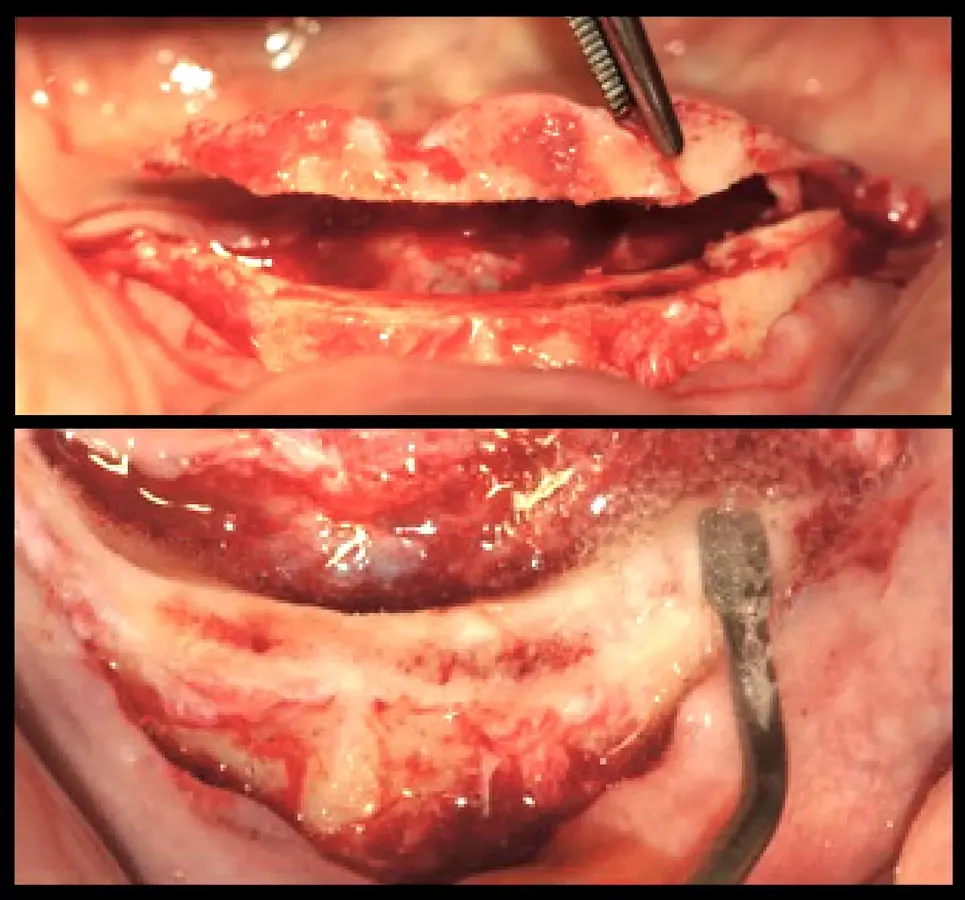

Paciente de ochenta y dos años de edad, de sexo masculino, acudió a la consulta odontológica refiriendo la necesidad de una prótesis inferior y malestar con la prótesis fija superior maxilar. El paciente refirió que le diagnosticaron diabetes mellitus tipo 2 hace 15 años. Refirió también haber tenido carcinoma de próstata y haber recibido radioterapia, hormonoterapia y orquiectomía. La última dosis de radioterapia la había recibido hace 72 meses y fue de 78 Gy en total. El paciente tenía un ASA2 según la clasificación del estado físico de la Sociedad Americana de Anestesiología (ASA)8,9. Asímismo, autorizó la recolección de la información y el uso de fotografías para su publicación con la firma de un consentimiento informado. En la evaluación intraoral, se observó coronas metal cerámicas tipo veneer en las piezas superiores con mala adaptación, acúmulo de placa bacteriana y edentulismo mandibular. Se inició el tratamiento con la motivación e instrucción de higiene oral, se procedió con la eliminación de las bolsas periodontales mediante raspado y alisado radicular. Estabilizada la salud periodontal, se realizó el alargamiento de las coronas clínicas. La gingivectomía se realizó con el electrobisturí (Servotome, Acteon), mientras que para el remodelado óseo se utilizaron los insertos P2LD del piezoeléctrico (Piezomed, W&H) (Figura 2).

El procedimiento quirúrgico se inició con la asepsia y antisepsia del campo operatorio y del paciente. A continuación, se colocó anestesia infiltrativa a nivel de la proyección de salida de los agujeros mentonianos, se procedió con la incisión y decolado. Se realizó la delimitación y regularización del reborde óseo mediante el inserto aserrado B7 y el subsiguiente remodelado del reborde crestal mediante el inserto plano diamantado S1 del piezoeléctrico Piezomed (W&H) (Figuras 4 y 5).